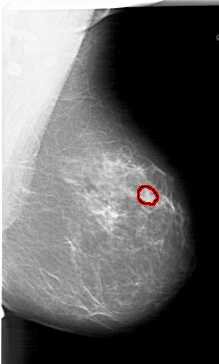

A_1767_1.LEFT_MLO

LEFT_MLO LINES 5821 PIXELS_PER_LINE 3736 BITS_PER_PIXEL 12 RESOLUTION 43.5 NON_OVERLAY

FILE: A_1767_1.RIGHT_MLO.OVERLAY

TOTAL_ABNORMALITIES 1

ABNORMALITY 1

LESION_TYPE MASS SHAPE OVAL MARGINS CIRCUMSCRIBED

ASSESSMENT 3

SUBTLETY 3

PATHOLOGY BENIGN

TOTAL_OUTLINES 1

BOUNDARY